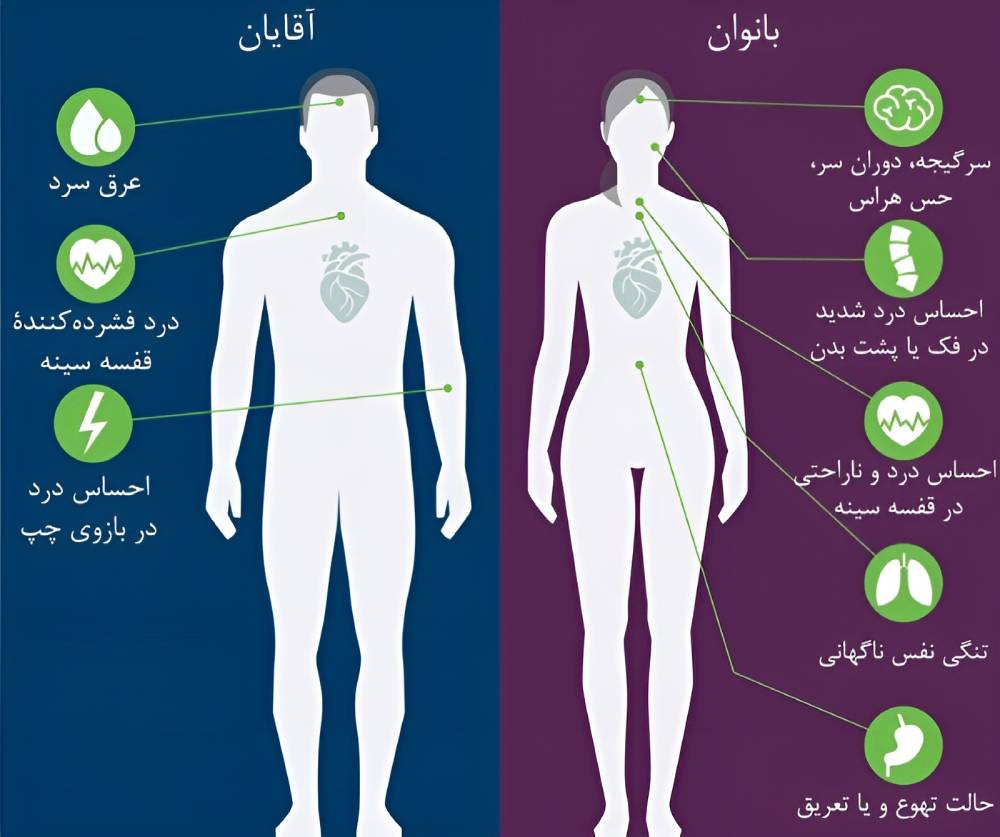

علائم سکته قلبی

علائم سکته قلبی متغیر است. علائم برخی بیماران خفیف و علائم عدهای شدید است؛ تعدادی از بیماران نیز هیچگونه علائمی را تجربه نمیکنند.

علائم شایع سکته قلبی به شرح زیر است:

- احساس درد در قفسه سینه که شبیه به فشار، گرفتگی، درد، فشردگی یا دردی عمیق و مداوم است.

- احساس ناراحتی یا دردی که در شانه، بازو، پشت بدن، گردن، فک، دندانها یا گاهی بالای شکم منتشر میشود.

- عرق سرد

- دوران سر یا سرگیجۀ ناگهانی

- اضطراب یا حس فاجعۀ قریبالوقوع

- حالت تهوع

- تنگی نفس

علائم سکته قلبی در بانوان

پژوهشهای پزشکیای که در سالهای گذشته انجام شده است، نشان میدهد احتمال اینکه بانوان دچار احساس ناراحتی یا دردی شبیه به سوءهاضمه در قفسه سینه شوند، کمتر است. احتمال دچار شدن بانوان به تنگی نفس، خستگی مزمن و بیخوابیای که قبل از سکته قلبی شروع میشود، بیشتر است. بهعلاوه بانوان دچار حالت تهوع و استفراغ یا احساس درد در پشت بدن، شانهها، گردن، بازوها یا شکم میشوند. نخستین علامت سکته قلبی گاهی ایست قلبی ناگهانی است.